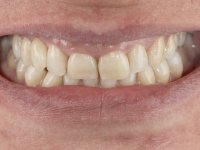

Female patient, 43 years old, non-smoker. Showed an edentulous space in the upper right canine area, resulting from tooth 1.3 impaction. The space had a mesio-distal diameter reduced to the normal size of the upper canine. This is consistent with the presence in the arch of the deciduous canine up to two years ago). Orthopantomography allows clearly view of tooth 1.3 impaction.The patient has a thick gingival phenotype and tolerable oral hygiene.

To define the dental zone to be covered by the Maryland bridge retainers, the patient was asked to perform maximum intercuspidation movements, and the contact points were marked with articular paper. Tooth preparation of the interproximal surfaces was made, to create a prosthetic insertion axis. It was sought that the mesio-distal diameter at the incisal level was equal to the diameter mesio-distal at the cervical level, that is to say, the interproximal walls were parallelized. Tooth preparation was done with fine grain diamond drills, and later polishing was done with abrasive discs. Color information was collected even before confection of the impression, to avoid dehydration of the arcade. Definitive impression was made using wash technique impression with silicone of heavy and regular consistency, both with fast setting, and a working plaster model was prepared in the lab. A laboratory scanner was used to scan the working model, and later, the infrastructure for the Maryland bridge was made using a CAD-CAM process. Ceramic was placed on this subframe. A ceramic adhesive was applied to the internal surface of the wings and connectors, which would enable bonding to the adjacent teeth. The adhesive bridge was bonded in the mouth following the conventional bonding technique. After bonding, the protrusion and laterality movements were carefully checked to avoid undesirable contacts.